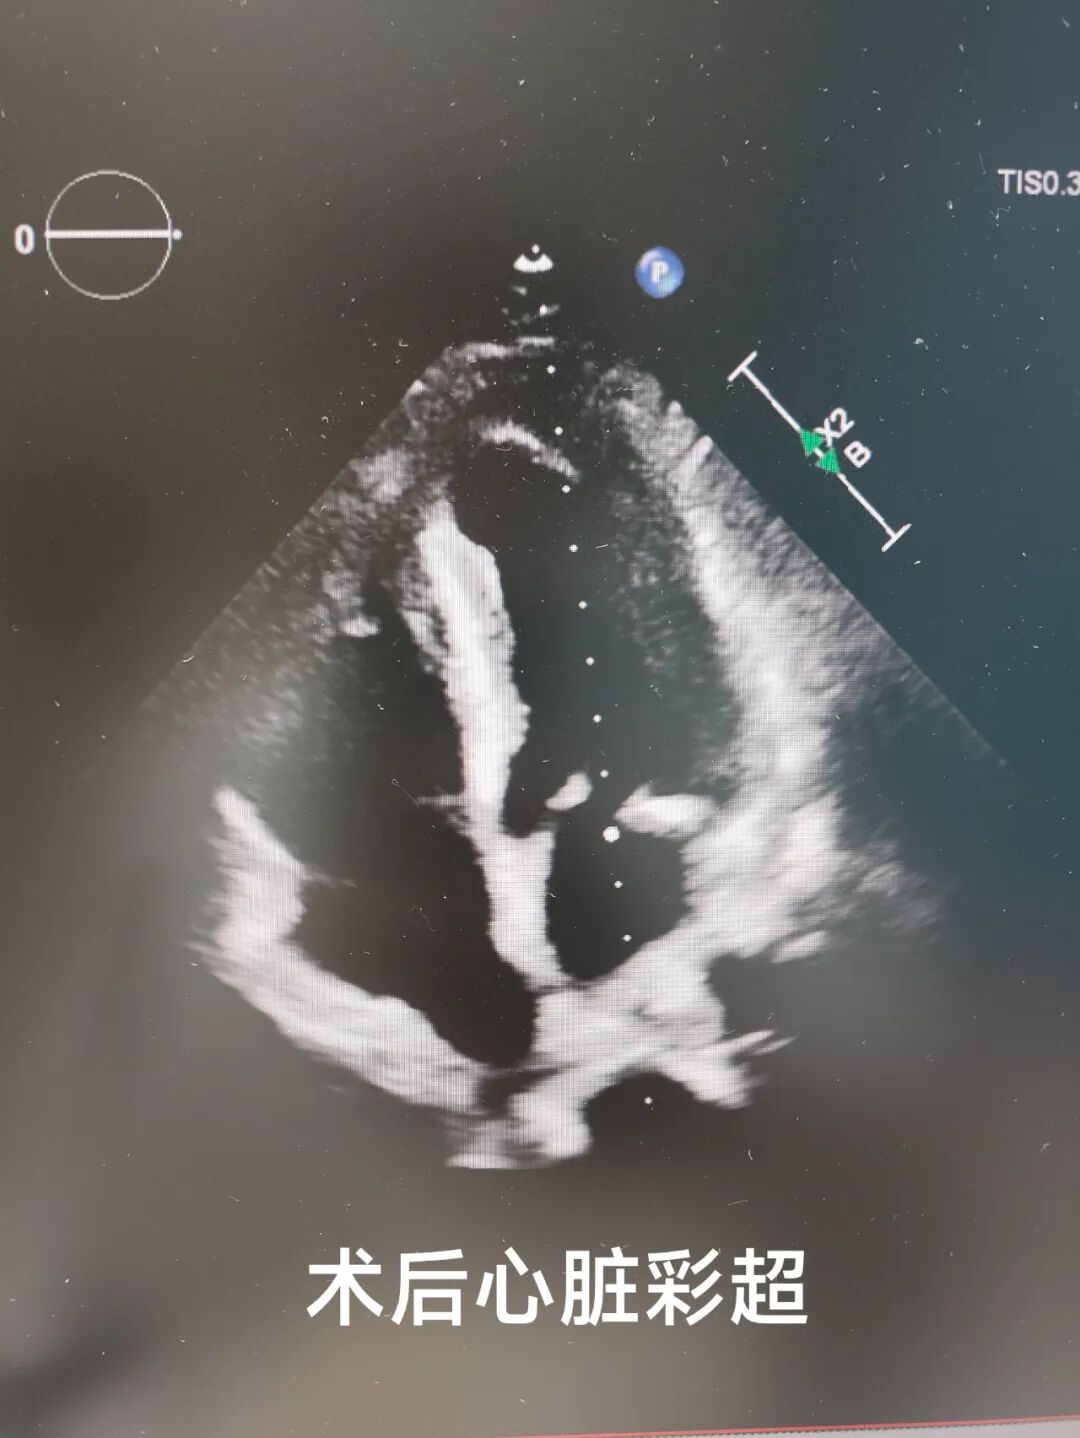

轉(zhuǎn)入心外科后完善術(shù)前準(zhǔn)備,在心血管醫(yī)學(xué)中心心臟大血管外科胡名松主任的主持下,經(jīng)心內(nèi)科、內(nèi)分泌科、麻醉科、CCU、手術(shù)室、心臟彩超室多學(xué)科會診全面評估后,心外科團(tuán)隊為患者實施高難度“冠狀動脈旁路移植+室間隔缺損修補(bǔ)術(shù)+室壁瘤切除術(shù)”。術(shù)中成功修補(bǔ)12mm室間隔穿孔,切除異常室壁組織,并完成冠脈血管重建,手術(shù)過程順利,術(shù)中食道超聲實時驗證分流消失。

術(shù)后,患者轉(zhuǎn)入CCU密切監(jiān)護(hù),團(tuán)隊動態(tài)調(diào)整治療方案,預(yù)防感染、維持電解質(zhì)平衡,并逐步康復(fù)訓(xùn)練。經(jīng)多學(xué)科聯(lián)合照護(hù),患者心功能顯著改善,呼吸困難消失,雜音減弱,術(shù)后復(fù)查顯示心臟結(jié)構(gòu)修復(fù)良好,最終順利轉(zhuǎn)入普通病房。